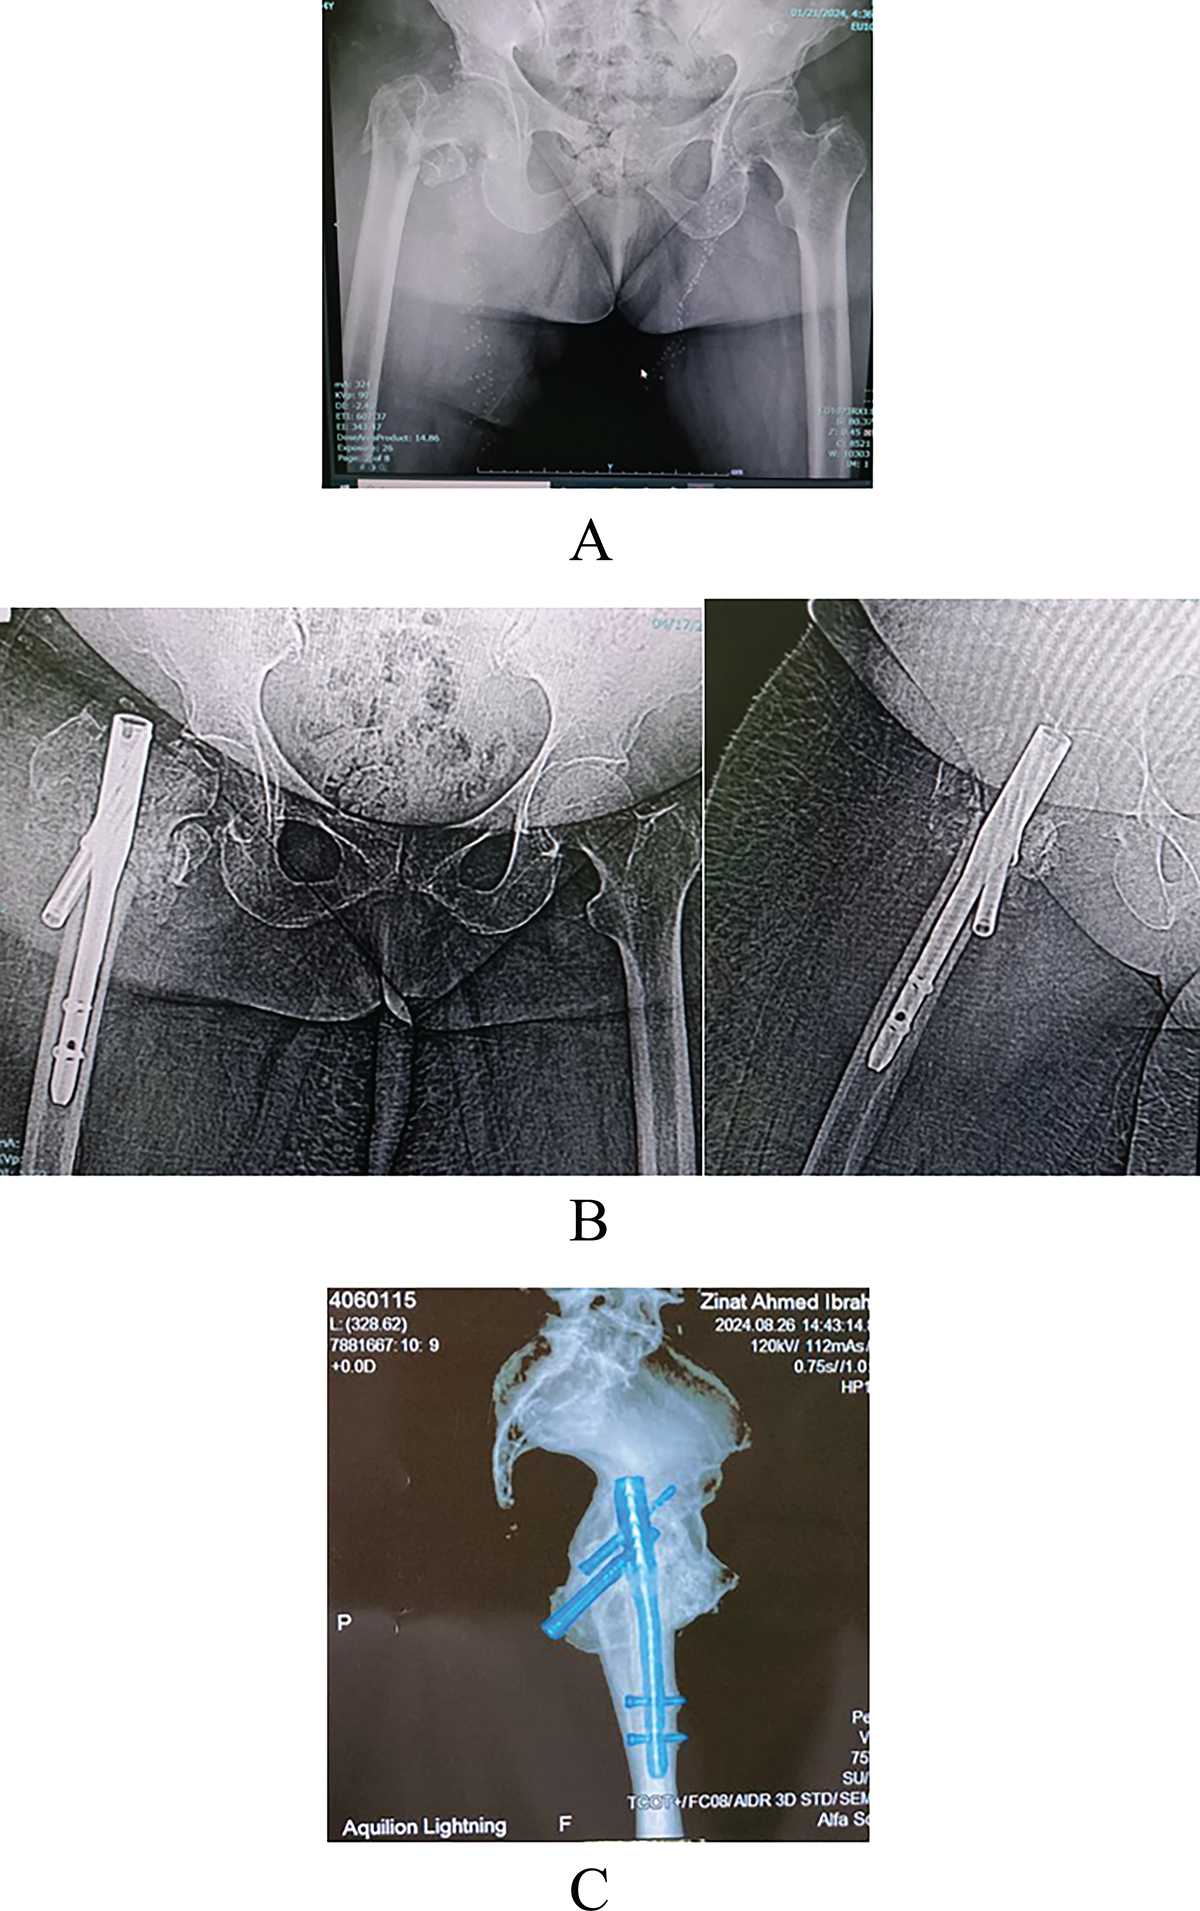

Figure 4

(A) (AO 31–A2.3) fracture pattern, (B) AP and lateral views 2 m later post-surgery showing AVN and varus collapse, and (C) CT 3D showing z effect.